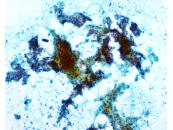

種別:呼吸器

出題:○古賀 裕1、山本 将義2、藤本 翔大2.1国立病院機構 九州がんセンター 病理診断科、2国立病院機構 九州がんセンター 臨床検査科

| 採取部位 | 肺腫瘍 | 採取方法 | 捺印 |

既往歴:59歳 前立腺癌に対してホルモン治療、放射線治療、59歳高血圧、63歳糖尿病で内服加療中

現病歴:前立腺癌の経過観察のCTにて右肺結節を指摘された。PSA含めて腫瘍マーカーは正常であった。本標本は術中迅速組織診断用に提出された肺腫瘍の捺印細胞診検体である。

| 正解 | 5.転移性肺腫瘍(前立腺癌) |